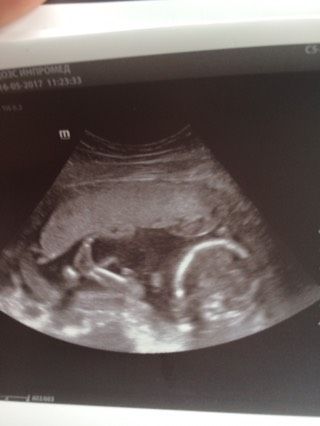

Наконец-то мы дождались второго скрининга и увидели своего кроху? малыш очень активный, врач сказала с характером) не нравилось ему что-то свернулся калачиком и не давал себя измерить, но врач его ласково попросила показаться и он тут же расправился и дал себя измерить))) весим мы 440 гр)) на 19 недель тянем) КТР 13,4, лежит малыш как положено) очень активный, пинал меня ногами все УЗИ) ну и конечно то, чего мы так долго ждали это пол))) врач сказала что мы ждём мальчика, но 100% она скажет после 26 недели) ну и фото, это просто мимими) врач сказала как на курорте лежит))) и что смазливый он у нас))))

ножку как хорошо видно )))) а я вот на втором скрининге не видела свою лялечку, муж зато смотрел в монитор… а для мамочек нет там условий… ээх!!! на третий скрининг хочу сходить в платную клинику, там боооольшой экран для меня есть))))

Обалдеть, так ножку видно хорошо) )

И не говорите, врач ножку уловить смогла хорошо)))

Ох какая ножка сладкая ?

Ути какая нооожка!!! Божечки!!)))))?